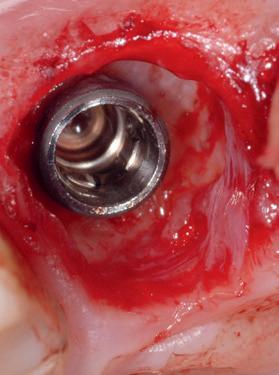

Een 48-jarige gezonde vrouw presenteerde zich in de nazorgfase 2 jaar na initiële behandeling met pockets van 6–7 mm en furcatieproblematiek bij de 47 en 46 (afbeelding 1.1 en 1.3). Bloeding bij sonderen was aanwezig, maar de patiente wilde geen chirurgische behandeling. Ze hield er een keurige mondhygiëne op na en kwam trouw iedere drie maanden voor nazorg.

De pockets werden onder lokale anaesthesie behandeld met een combinatie van ultrasoon en handinstrumentarium volgens de hierboven beschreven methode. De natriumhypochloriet/aminozuur-gel werd vijfmaal aangebracht en na iedere applicatie mechanisch verwijderd. Daarna werd de pocket gevuld met cross-linked hyaluronzuur.

Na 6 maanden was de pocketdiepte teruggebracht tot 3 mm en was er geen bloeding na sonderen waarneembaar. Een recessie van 2 mm was aanwezig. Röntgenologisch was er nieuw bot zichtbaar (afbeelding 1.2 en 1.4).